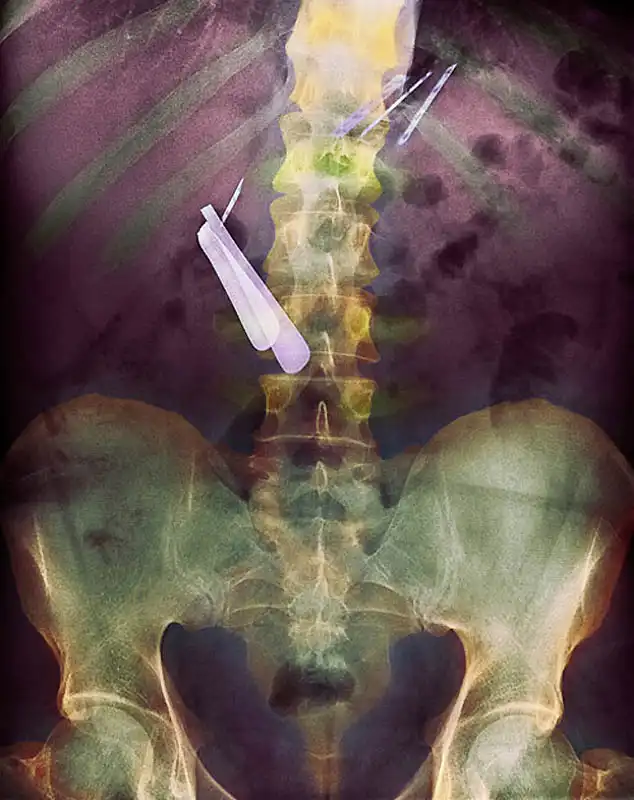

Цветной снимок предметов, которые проглотил пациент, и которые застряли в его кишечнике, включая ложку и лезвие.

Цветной рентген желудка пациента, который проглотил бритву (по центру слева) и лезвия (вверху справа).